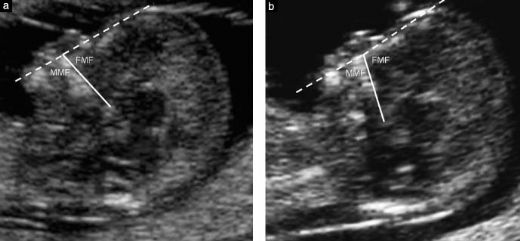

2. Anne Karnında Down Sendromu Belirtileri Anne karnında Down sendromu belirtileri, çeşitli prenatal tarama testleri ve görüntüleme yöntemleri ile belirlenebilir. Aşağıda bu belirtiler sıralanmıştır:

3. Prenatal Tarama Testleri Hamilelik sırasında Down sendromunu tespit etmek için çeşitli tarama testleri uygulanmaktadır. Bu testler, risk oranlarını belirlemeye yardımcı olur ve kesin tanı için daha ileri testlere yönlendirebilir: